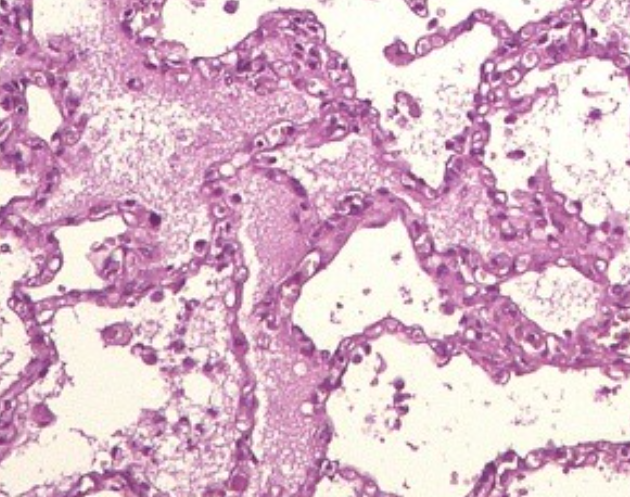

В рамках данного исследования в качестве источника реальных данных были использованы микроскопические изображения легких, предоставленные Бюро судебно-медицинской экспертизы г. Байконур (рисунки 2, 3). Визуальный анализ подтверждает, что предложенный автоэнкодер лучше сохраняет границы объектов и текстурные структуры по сравнению с традиционными фильтрами.

На рисунках 2 и 3 изображены микроскопические снимки легких до и после фильтрации.

Рисунок 2 - Изображение до фильтрации

Однако на практике получаемые изображения часто характеризуются наличием различных искажений — шумов, размытости, пониженного контраста и других артефактов, обусловленных как техническими ограничениями микроскопического оборудования, так и условиями съёмки. Эти факторы затрудняют визуальную интерпретацию и автоматизированную обработку изображений, снижая точность диагностических и экспертных выводов.